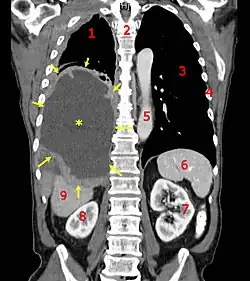

Se sabe que respirar aire con asbesto puede aumentar el riesgo de cáncer en seres humanos. Hay dos tipos de cáncer producidos por exposición al asbesto: cáncer de pulmón y el mesotelioma.

1. Pulmón derecho,

2. Columna vertebral,

3. Pulmón izquierdo,

4. Costillas,

5. Aorta,

6. Bazo,

7. Riñón izquierdo,

8. Riñón derecho,

9. Hígado.

Los primeros informes que relacionaban el cáncer de pulmón y el asbesto datan de 1935.[25] El cáncer producido por el asbesto no aparece inmediatamente, sino que se manifiesta después de varios años (el mesotelioma pleural suele tener un tiempo de latencia de 20 a 40 años). Los estudios en trabajadores sugieren también que respirar asbesto podría aumentar las posibilidades de contraer cáncer en otras partes del cuerpo (estómago, laringe, intestino, esófago, páncreas y riñones). La identificación y el tratamiento tempranos de todo cáncer pueden aumentar la calidad de vida y la supervivencia de la persona.

Los síntomas habituales son: pérdida de apetito y de peso, cansancio, dolor torácico, hemoptisis o expectoración de sangre y dificultad respiratoria.

Se planteó que la combinación de exposición al asbesto y al humo de cigarrillo aumentaba considerablemente las posibilidades de contraer cáncer de pulmón, aunque se considera en esta combinación al asbesto como el principal causante de la muerte, por encima del hábito tabáquico. Generalmente las empresas productoras se escudan, aún en la actualidad, en la posible incidencia del tabaquismo en el desarrollo del cáncer, pues la mayoría de la población fabril era fumadora en las épocas de mayor utilización del amianto. Diversas sentencias judiciales han descartado, dependiendo de los niveles de exposición, que la incidencia del hábito tabáquico sea superior a la del amianto para el desarrollo del cáncer de origen laboral.